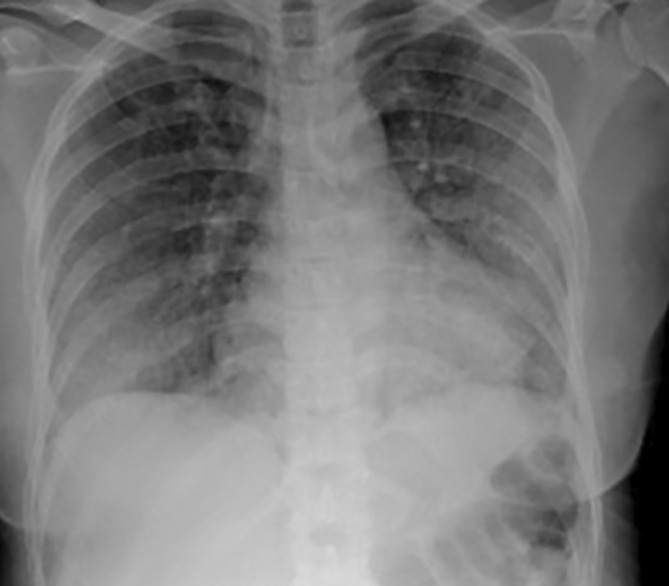

Bleomycin-induced lung injury (BILI) is a well-recognised but potentially life-threatening complication of ABVD chemotherapy (adriamycin, bleomycin, vinblastine and dacarbazine), often requiring prompt diagnosis and intervention. We present a case of a 43-year-old female with Hodgkin's lymphoma who developed progressive respiratory symptoms following her fourth cycle of ABVD. A broad infectious and autoimmune workup was unremarkable, and chest imaging was consistent with interstitial lung disease. Her condition deteriorated despite empirical antibiotics and high-dose corticosteroids. The addition of rituximab and pirfenidone led to significant clinical and radiological improvement, highlighting the potential role of these agents in managing steroid-refractory BILI.